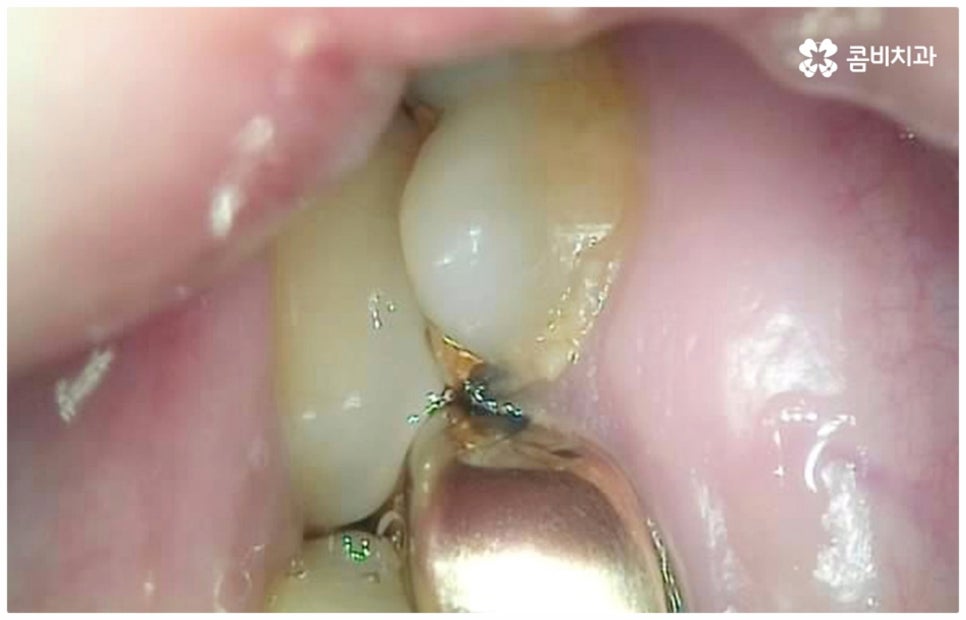

모든 치아가 각자의 역할을 가지고 있지만 특히 어금니의 경우 가장 크고 단단하여 저작 기능의 핵심 역할을 맡고 있는 만큼 굉장히 중요한 치아라고 할 수 있습니다. 그런데 구강 가장 안쪽에 있기 때문에 관리하기가 까다롭고 평상시에도 음식물 찌꺼기가 남아있기 쉬워 주변 잇몸이 부어오르면서 염증이 생기거나 충치가 생길 가능성이 높은 치아라서 관리하실 때 특별히 주의하실 필요가 있어요. 충치가 한 번 발생하여 치아 안쪽으로 감염이 진행되면 통증이 점점 심해져서 나중에는 일상 생활이 어려워질 정도가 될 수도 있고 결국 치아뿌리염증으로 번져 발치를 해야하는 상황에 이를 수도 있기 때문에 발견 즉시 어금니충치치료 를 받아주시는 게 좋을 거예요.

병증이 초기 단계일 때는 치아 겉면인 법랑질이 일부 손상된 것이므로 해당 부위를 긁어낸 후 레진으로 채워주는 비교적 간단한 어금니충치치료 를 해주면 되며 환자분들의 상황에 따라 다르지만 보통 하루 만에 치료가 마무리되는 경우가 많기 때문에 시간과 비용적인 측면에서의 부담도 덜한 편이라고 할 수 있어요. 하지만 법랑질에는 신경이 없기 때문에 초기에는 자각 증상이 거의 없으며 겉으로 드러나는 특징도 두드러지지 않기 때문에 환자분들 입장에서 발견하기가 쉽지 않으므로 주기적으로 검진을 받아 혹시라도 자신이 모르는 사이에 충치가 진행되고 있지는 않은지 꼼꼼하게 살펴보시는 것이 초기 충치에 대처하실 수 있는 지름길이라고 할 수 있습니다.

만약 충치가 어느 정도 진행되어 상아질까지 손상되면 비로소 시리거나 쑤시는 듯한 통증이 생기며 이 때 치과에 내원하시면 정도에 따라 감염 부위를 제거하고 어금니충치치료 방법 중 인레이 또는 온레이를 통해 수복하게 되는데, 이 시기를 지나 병증이 더욱 심해지면 내부 치수조직을 제거하는 신경치료를 진행하게 될 거예요.